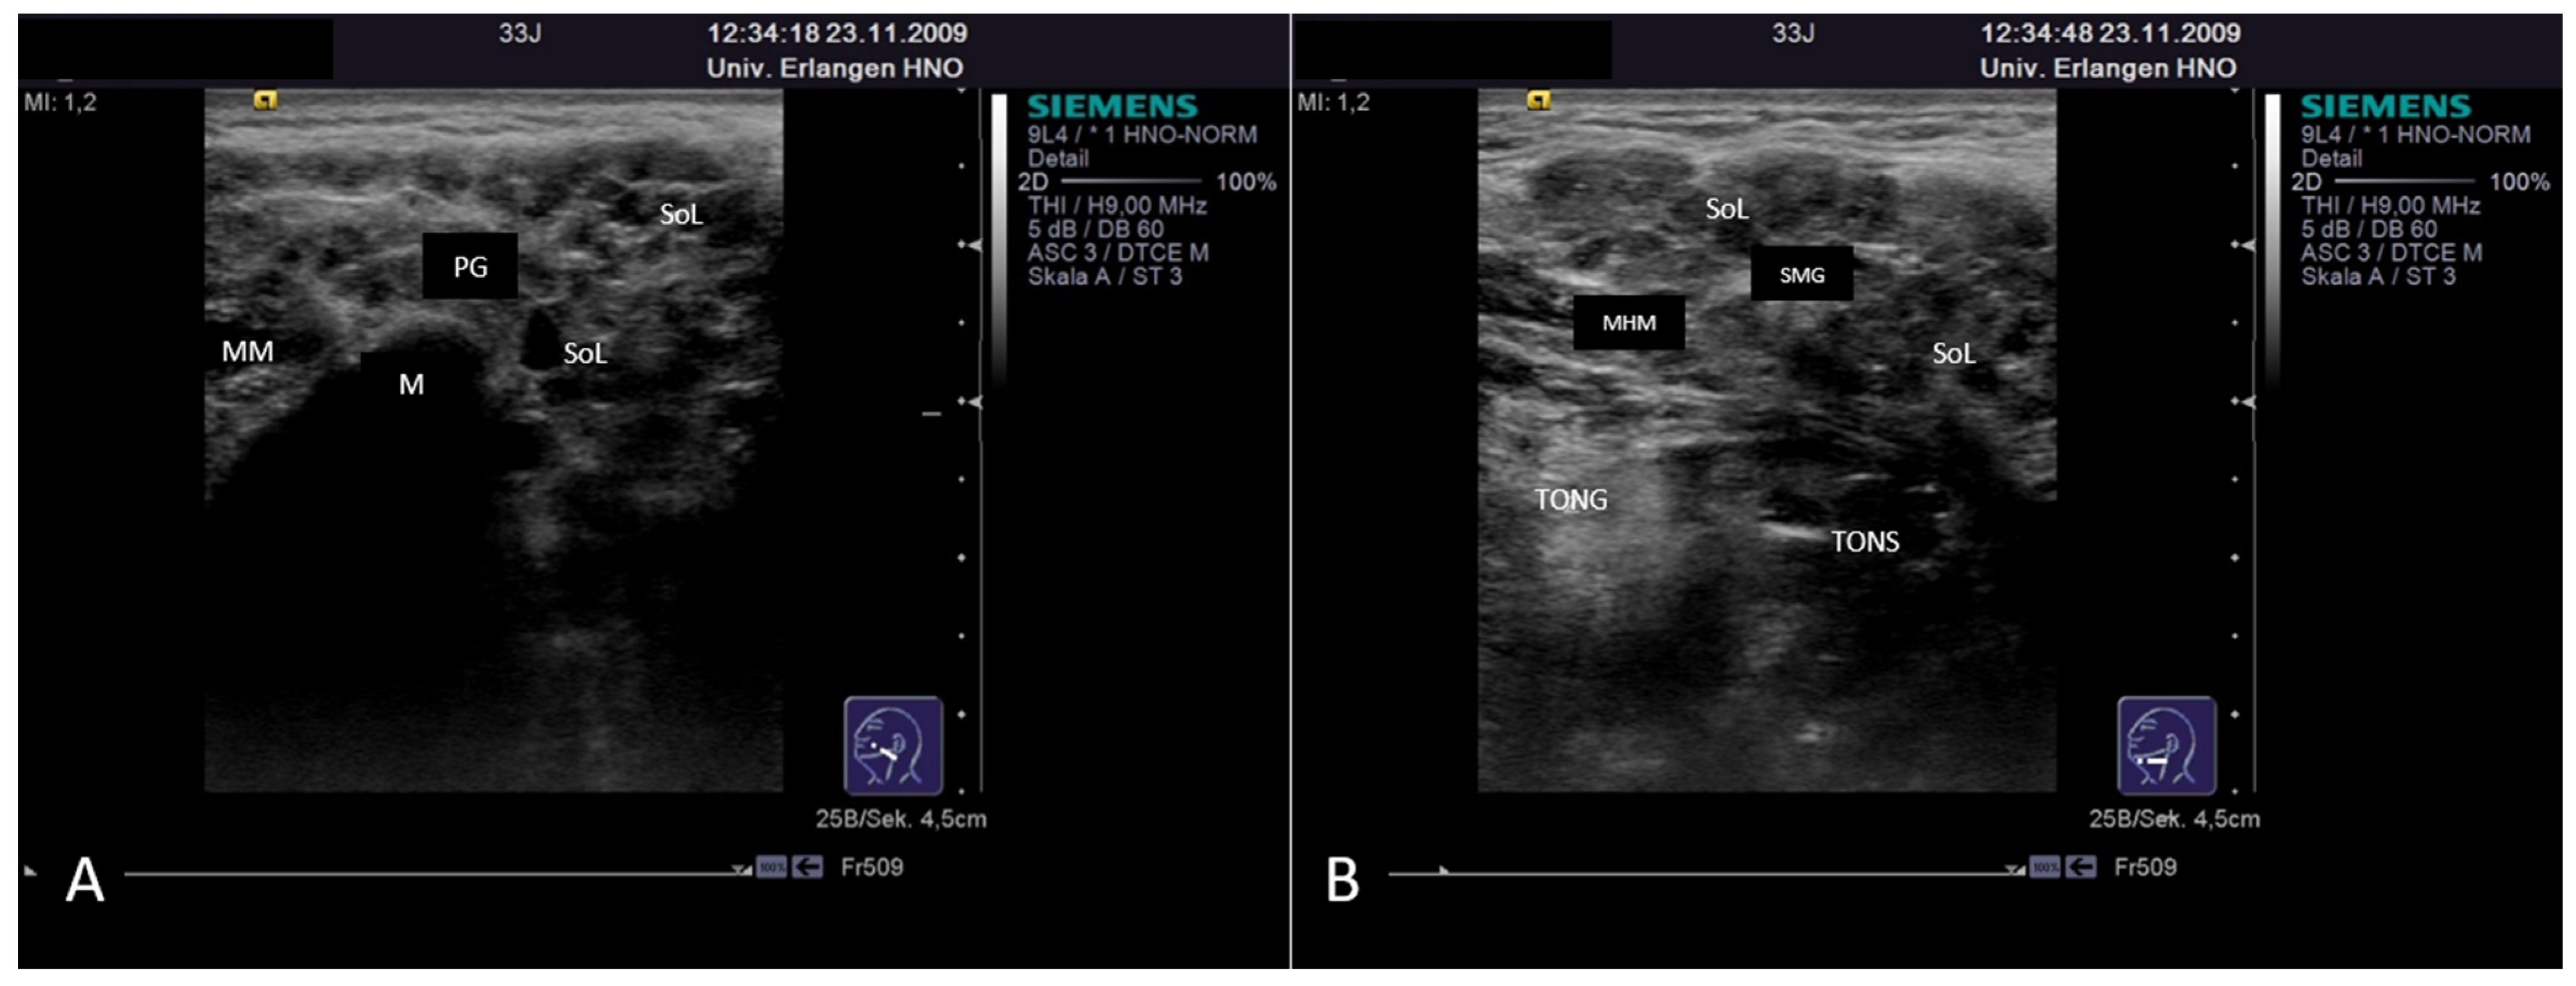

3.4.2. Chronic Recurrent Juvenile Parotitis

3.4.3. Sjoegren’s Syndrome/Disease